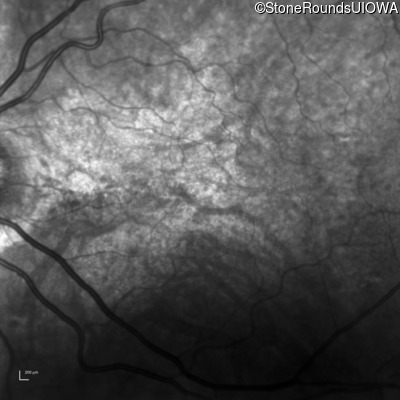

Age at visit: 58 years